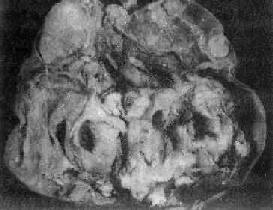

肉眼观,肿多为囊性、中等大小,表面光滑,囊内含毛发团及皮脂样物(图13-22)。囊壁较厚,内侧常有一处突起的结节或我称头节,表面被覆鳞状上皮,结节内常有毛发、牙或骨质等。肿多数为单房。镜下,可见到三胚层各种类型的成熟组织,其中以皮肤、皮脂腺、汗腺、毛囊及脂肪最多见;其次为软骨、神经胶质、神经细胞、骨及呼吸上皮;其他如甲状腺、胃肠上皮及牙等较少见。

图13-22 卵巢囊性畸胎

囊内充满含有毛发的黄色油脂样物